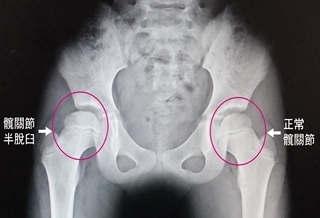

(優活健康網記者徐平/綜合報導)一名小六孩童因青少年原因不明型脊柱側彎(AIS),外觀出現明顯高低肩,家長以為是姿勢不良造成,糾正坐姿與站姿仍無法改善。經檢查後得知該名孩童骨密度偏低,骨質流失、骨骼支撐力相對差,無法負荷身體重量,而導致脊椎側彎更不易矯治,引發高低肩。學齡孩童鈣質的攝取量不足也可能是原因之一,家長可讓孩童每日飲用2份鮮乳,攝取足夠鈣質維持骨骼正常發育。鈣質攝取不足造成脊椎側彎、駝背、OX型腿根據台灣家庭醫學會資料顯示,脊椎側彎的盛行率約3-5%,國民健康署2014調查也顯示,台灣7至12歲學齡孩童近100%鈣質攝取不足,振興醫院骨科主治醫師朱唯廉表示,脊椎側彎也有可能進一步引發高低肩、骨盆傾斜或長短腳等情況,影響孩童外觀與健康發育。多數家長習慣將這些現象歸咎為姿勢不良,卻忽略鈣質對於骨骼支撐力的影響性。振興醫院骨科主治醫師朱唯廉提醒,孩童在成長過程中,鈣質則是骨骼礦化過程中關鍵營養素,若缺少鈣質將影響骨質密度與骨骼支撐力。若隨著孩童增高、增重,在骨骼支撐力不足情況下,不僅高低肩、長短腳,也可能會引發駝背、OX型腿等現象。營養均衡、睡足8小時、多運動、要日曬朱唯廉醫師表示,上述孩童的每日飲食不僅沒有攝取足夠鈣質的習慣也很少運動。除了透過攝取足夠鈣質、蛋白質、飲食均衡之外,孩童也應每天睡足8小時、多做彈性運動如打籃球、跳繩、每天日曬10~20分幫助改善,讓孩童骨骼正常發育。營養師:應每天2份鮮乳 補充鈣質台北市居家照護營養師程涵宇強調,鮮乳是孩童成長不可獲缺的飲品,同時也是人體鈣吸收最好的飲品,國健署建議每日應攝取1.5~2份奶。根據最新調查顯示,學童每日僅攝取0.7份,不達每日建議量。程涵宇營養師表示,家長應把握高中前的成長發育階段,讓學童每天攝取2份鮮乳,才能打好基礎,避免兒童骨鬆影響發育。